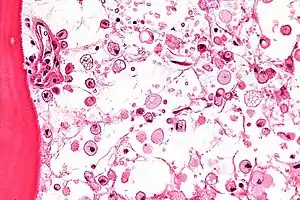

The disease is caused by a defect in housekeeping gene for lysosomal glucocerebrosidase (also known as beta-glucosidase, EC 3.2.1.45, PDB: 1OGS) on the first chromosome (1q22). The enzyme is a 55.6-kilodalton, 497-amino acid-long protein that catalyses the breakdown of glucocerebroside, a cell membrane constituent of red and white blood cells. In Gaucher disease, the enzyme is unable to function correctly and glucocerebroside accumulates. The macrophages that clear these cells are unable to eliminate the waste product, which accumulates in fibrils, and turn into 'Gaucher cells', which appear on light microscopy to resemble crumpled-up paper.[3]

Micrograph showing crinkled paper macrophages in the marrow space in a case of Gaucher disease, H&E stain.

A diagnosis can also be implied by biochemical abnormalities such as high alkaline phosphatase, angiotensin-converting enzyme, and immunoglobulin levels, or by cell analysis showing "crinkled paper" cytoplasm and glycolipid-laden macrophages.